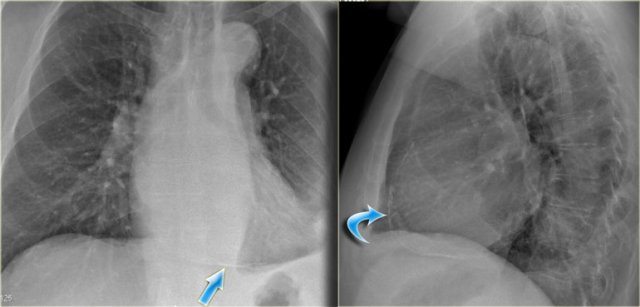

An important mediastinal-lung interface to look for is the azygoesophageal line or recess (arrow).

Azygo-esophageal recess

The azygo-esophageal recess is the region inferior to the level of the azygos vein arch in which the right lung forms an interface with the mediastinum between the heart anteriorly and vertebral column posteriorly.

It is bordered on the left side by the esophagus.

Deviation of the azygoesophageal line is caused by:

- Hiatal hernia

- Esophageal disease

- Left atrial enlargement

- Subcarinal lymphadenopathy

- Bronchogenic cyst

Notice the deviation of the azygoesophageal line on the PA-film.

It is caused by a hiatal hernia.

The arrow point to the barium contrast within the hiatal hernia.